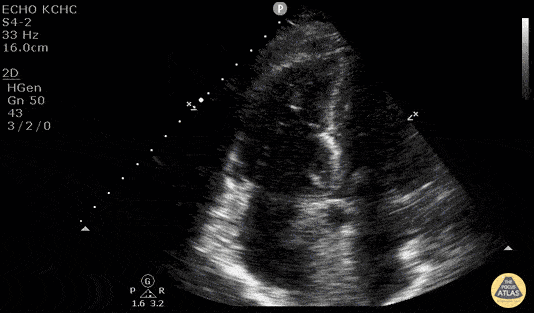

Right Ventricular Dysfunction - McConnell's Sign - Pulmonary Embolism

Elderly patient with chest pain, sob, and HR in 120’s. During ER stay became hypotensive with systolic in 80’s. POCUS demonstrated RV enlargement and McConnell’s Sign - systolic akinesia of the RV free wall with preserved functioning of the apex. This is concerning for acute PE. Patient became progressively hypotensive and TPA was pushed. Dr. Kelly Maurelus, Matthew Riscinti - Kings County Emergency Medicine